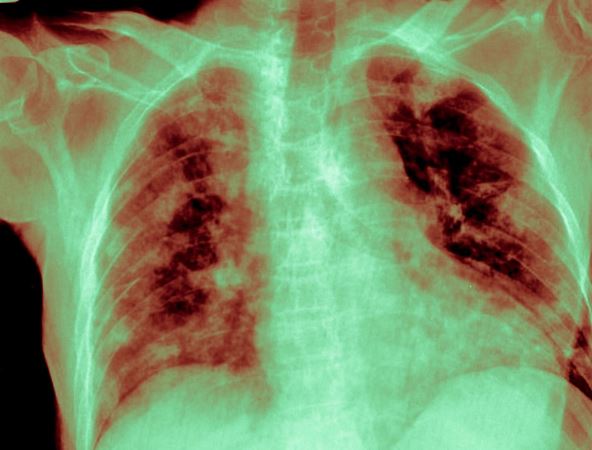

grafički prikaz zdravih pluća i pluća sa fibrozom

Pluća pogođena fibrozom su poput debelih, krutih balona u koje je potreban ogroman napor da bi se uveo vazduh Foto: Shutterstock